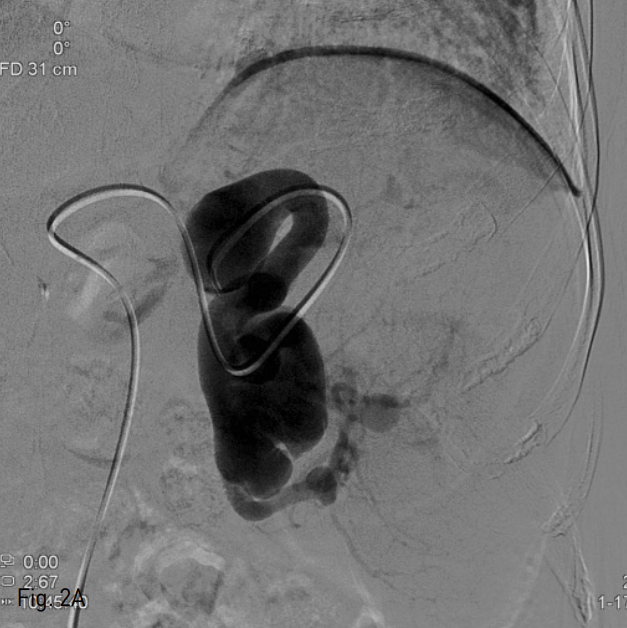

우측 총대퇴동맥을 천자한 후, 5 Fr sheath (Terumo, Tokyo, Japan)를 거치 시켰다. 이후 0.035 inch guide wire (Terumo, Tokyo, Japan)와 5 Fr Roche-Hepatic ca theter (Cook, Bloomington, IN, USA)를 이용하여 비장동맥 조영술을 시행하였으며, 근위부 1/3 지점에 약 4cm 크기의 가장 큰 비장동맥류가 관찰되었다 (Fig. 2A). 2.2 Fr microcatheter (Progreat; Terumo, Tokyo, Japan)을 이용하여 가장 원위부에 있는 동맥류를 지나 비장 문까지 진입한 후 11개의 nester coil (Cook, Bloomington, IN, USA)을 이용하여 색전을 시행하였다. 그 후 microcatheter를 근위부로 옮겨 가장 큰 비장동맥류의 원위부와 근위부에 13개의 nester coils, 1개의 vascular plug, 그리고 histoacryl 1:3 mixture를 이용하여 색전하였다. 색전술 후 복강 동맥 조영술 상 비장동맥은 완전히 색전되어 조영되지 않았으나, 가장 큰 크기의 비장동맥류에 지연기상 조영이 나타났다 (Fig. 2B). 이에 다시 2.2 F microcatheter를 우측 위그물막동맥으로 진입시켜 조영하였고, 많은 측부 곁가지에 의해 비장동맥류가 조영되었다 (Fig. 2C). 다시 histoacryl 1:5 mixture를 이용하여 색전하였으며, 복강동맥 조영술상 더 이상 비장동맥류는 관찰되지 않았다.

Fig. 2

A. Initial splenic arteriogram shows a large splenic artery aneurysm in proximal portion of splenic artery.